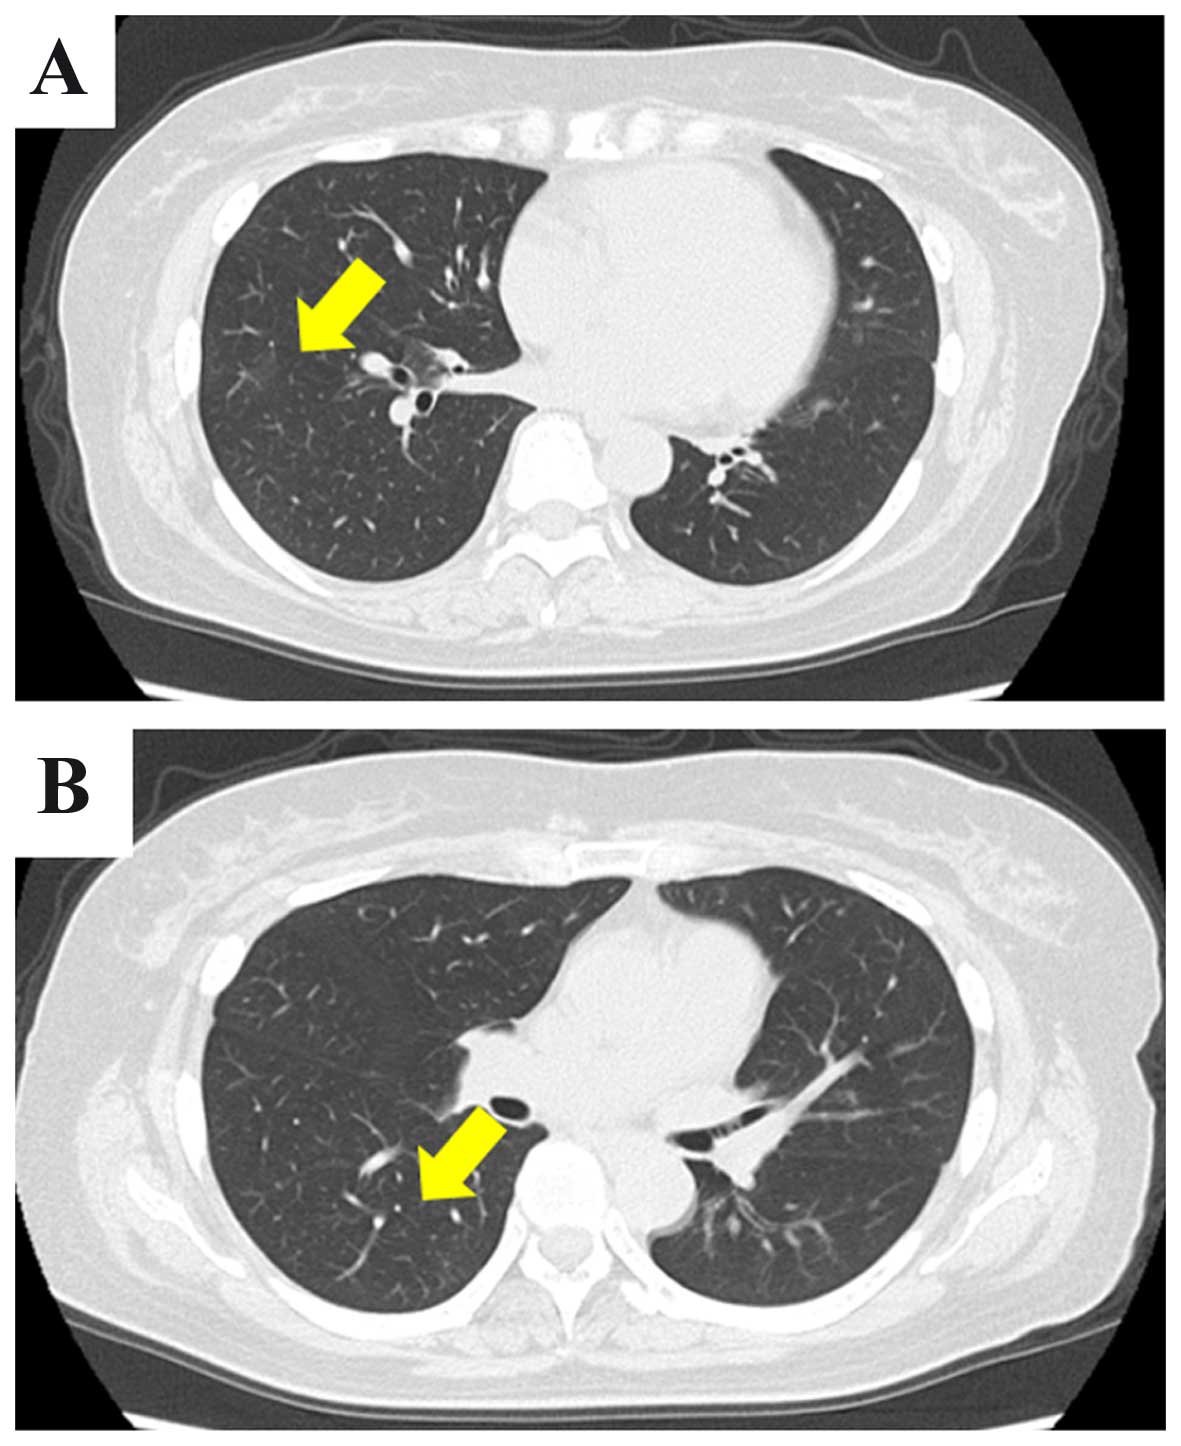

A 56-year old woman underwent medical examination by a physician. The patient was asymptomatic prior to hospitalization. Computed tomography (CT) was performed. Abdominal CT revealed a 22-mm mass with a cystic area in the right kidney and multiple enlarged lymph nodes in the common iliac, external iliac and groin areas bilaterally (Fig. 1A and B). The chest CT revealed multiple pulmonary nodules bilaterally, the largest measuring 15 mm (Fig. 1C and D). The laboratory tests revealed mild elevation of the C-reactive protein levels to 1.16 mg/dl (normal range, ≤0.14 mg/dl). The levels of tumor markers, such as squamous cell carcinoma antigen, carbohydrate antigen 19-9, carcinoembryonic antigen (CEA), cytokeratin 19 fragment and pro-gastrin-releasing peptide, were within the normal range. The serum concentration of soluble interleukin-2 receptor (sIL-2R) was increased to 914 U/ml (reference range, 122–496 U/ml). [18F] 2-fluoro-2-deoxy-d-glucose (18F-FDG) positron emission tomography showed high FDG uptake by multiple enlarged lymph nodes, whereas the right kidney mass and the pulmonary nodules exhibited no increased uptake. A right inguinal lymph node biopsy was first performed, since malignant lymphoma was suspected. On microscopic examination, there were sheets of lymphoid cells and numerous lymphoid follicles; however, there was no evidence of tumor cells (Fig. 2) and the lymph node enlargement was diagnosed as reactive lymphoid hyperplasia. Since the right renal tumor was suspected to be RCC, laparoscopic partial nephrectomy was performed, without any complications. The resected tumor was sized 25 mm and was well-circumscribed; histologically, it was composed of cells with eosinophilic cytoplasm arranged in glandular and cribriform patterns (Figs. 3 and 4). Immunohistochemically, almost all the tumor cells were diffusely positive for pancytokeratin (AE1/AE3), cytokeratin 7 and E-cadherin. Immunoreactivity for CD10, α-methylacyl-CoA racemase, 34βE12, c-kit, anaplastic lymphoma kinase, thyroid transcription factor-1, p63 and CEA was not detected in the tumor cells. These findings suggested that the tumor was a RCC with distal tubular characteristics. However, the findings were not typical. The case was referred for expert consultation, and the final pathological diagnosis was unclassified RCC. One month after surgery, a thoracic CT scan revealed spontaneous regression of the pulmonary nodules (Fig. 5). However, the enlargement of the lymph nodes did not subside. Surveillance CT scans at 3 months revealed no evidence of recurrence or progression of the pulmonary nodules and lymph nodes. In addition, the level of sIL-2R had decreased to 511 U/ml.

Figure 5.

(A and B) Thoracic computed tomography scan showing spontaneous regression of multiple pulmonary nodules compared with Fig. 1 (arrows).